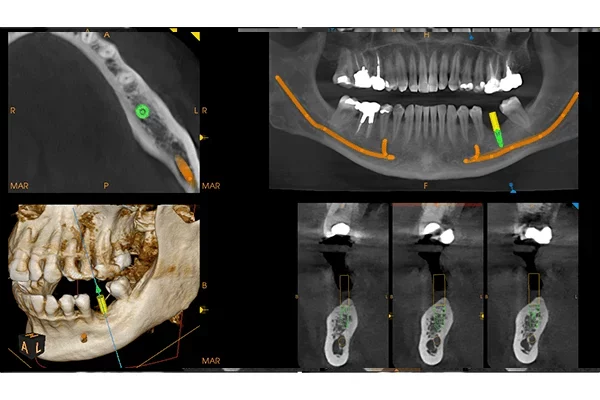

• MAR patentované potlačení artefaktů s živým náhledem efektu filtru pomocí nezávislého algoritmu 3D (zcela unikátní)